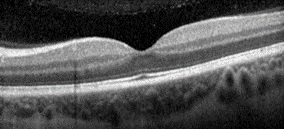

Figuur: Oogscan (OCT scan) van patiënt met CSC (linker afbeelding): een zwarte vochtophoping onder het netvlies (macula). Het witte lijntje daaronder is de pigmentcel-laag (RPE), waar het vocht doorheen lekt. Ter vergelijking de rechter afbeelding van een normaal netvlies.

- Een scan van de lagen van uw netvlies (OCT scan), om de vochtophoping optimaal in beeld te brengen (zie figuur op de vorige pagina).